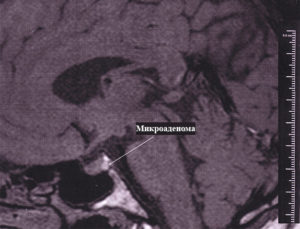

Правильно определить вид опухоли может только врач при помощи специальных исследований (МРТ, КТ, анализов на гормоны). Правильно подобранная терапия помогает полностью избавиться от заболевания.

При помощи МРТ легко определить наличие опухоли, ее размер. Регулярно посещая врача, необходимо следить за поведением новообразования.

- Первоначально проводится лабораторное исследование и на основании полученных результатов выбирают дополнительные методы диагностики, среди которых наиболее популярными являются МРТ и КТ.

При КТ или МРТ удаётся обнаружить опухоль с послойным строением ткани.